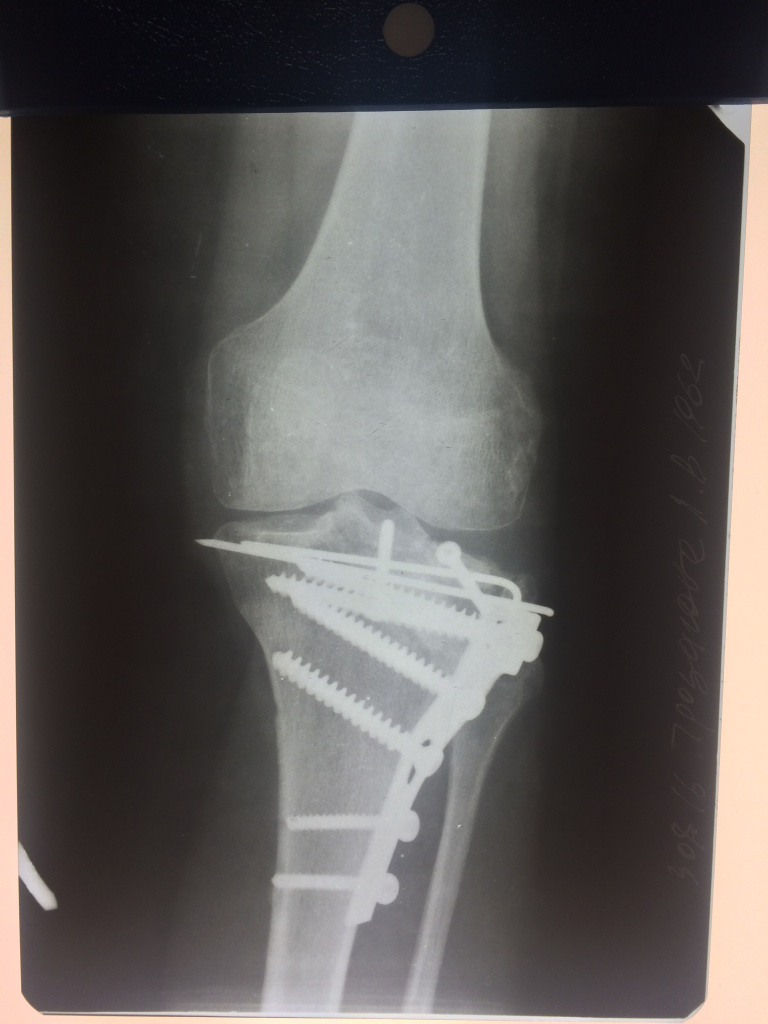

Использование материала Остеоматрикс при импрессионном оскольчатом переломе наружного мыщелка большеберцовой кости по типу Schatzker II

Использование материала Остеоматрикс при импрессионном оскольчатом переломе наружного мыщелка большеберцовой кости по типу Schatzker II.

Операция - открытая репозиция, остеосинтез большеберцовой кости опорной пластиной с костной ксенопластикой маетриалом "Остеоматрикс". На контрольных снимках в три и шесть месяцев имеется консолидация перелома, миграции фиксатора нет, имеется остеоинтеграция ксенопластического материала. Функция коленного сустава полная.